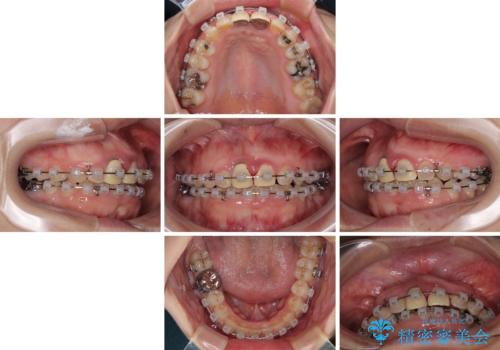

- 矯正装置

- クリアブラケット

- 2年2ヶ月

マウスピース装着は煩わしいとのことで、表側のワイヤー装置にて矯正治療を行うこととしました。